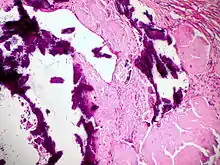

![]() Ausgeprägte Amyloidablagerungen (homogen rosa) in einem Lymphknoten, H&E. |

![]() Amyloidablagerungen in den Gefäßwänden, H&E. |